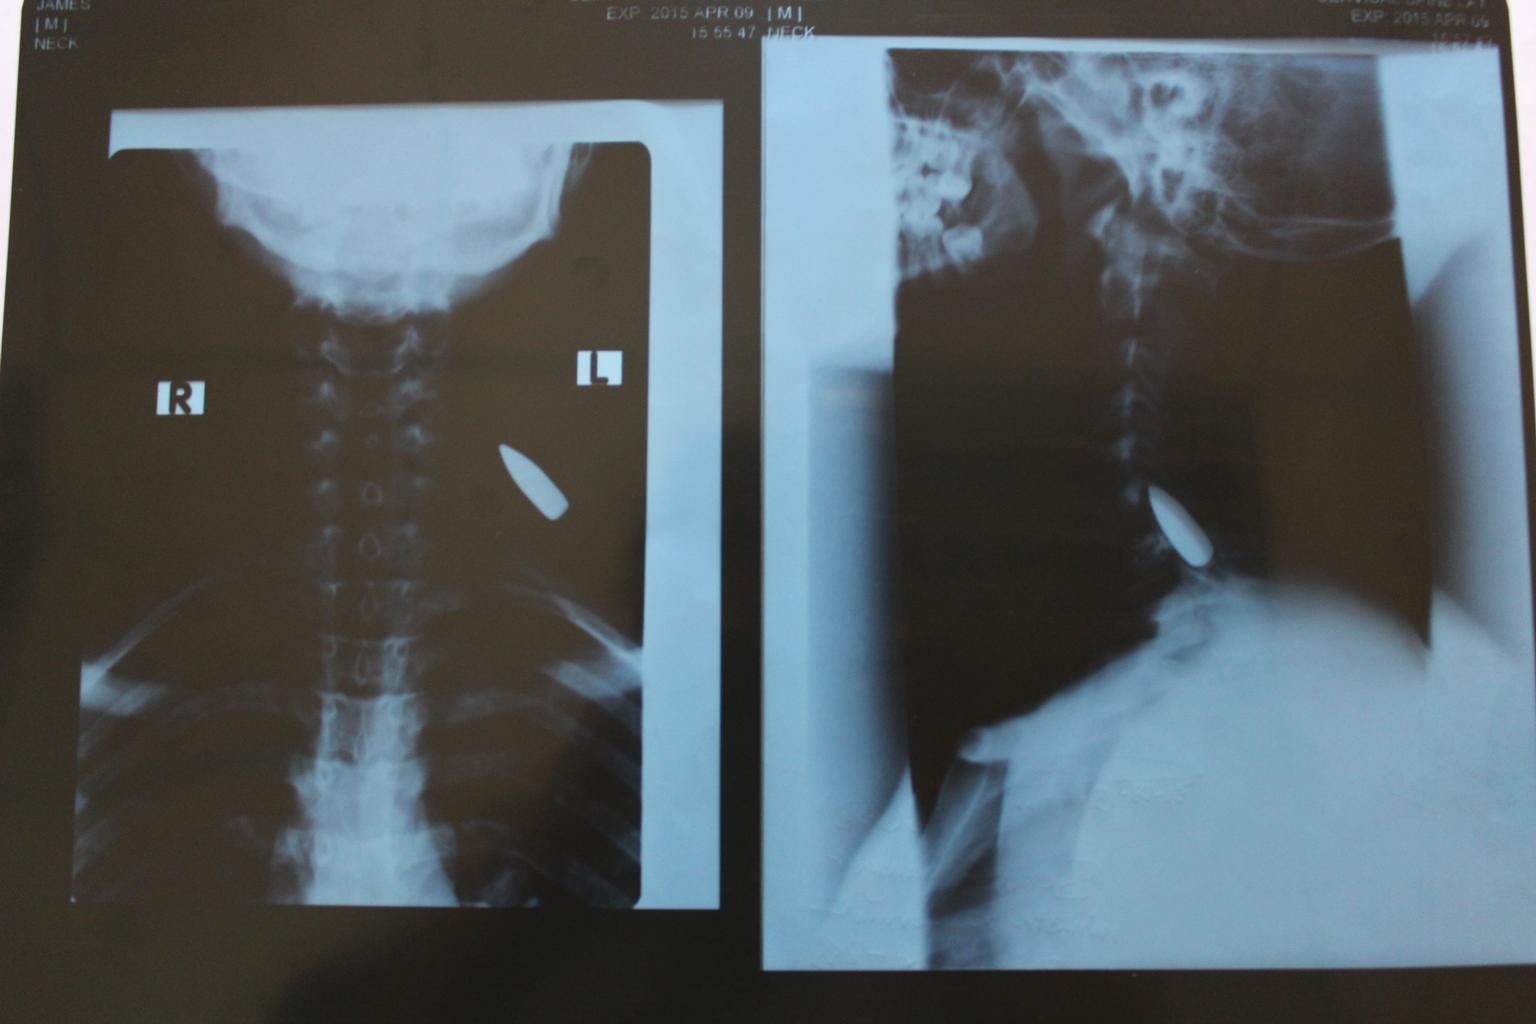

Boto*, 16, is undergoing treatment to have a bullet removed from his neck. He was shot during the two-year period he fought with the Cobra Faction rebel group, in South Sudan. “When they take the bullet, out I will feel safe. … If I am OK after my operation and I can go to school, I can become a doctor or a leader in my community. I might become an important person. I don’t want fighting, and I don’t want to be a soldier. I want to be a doctor and help many people,” he said.